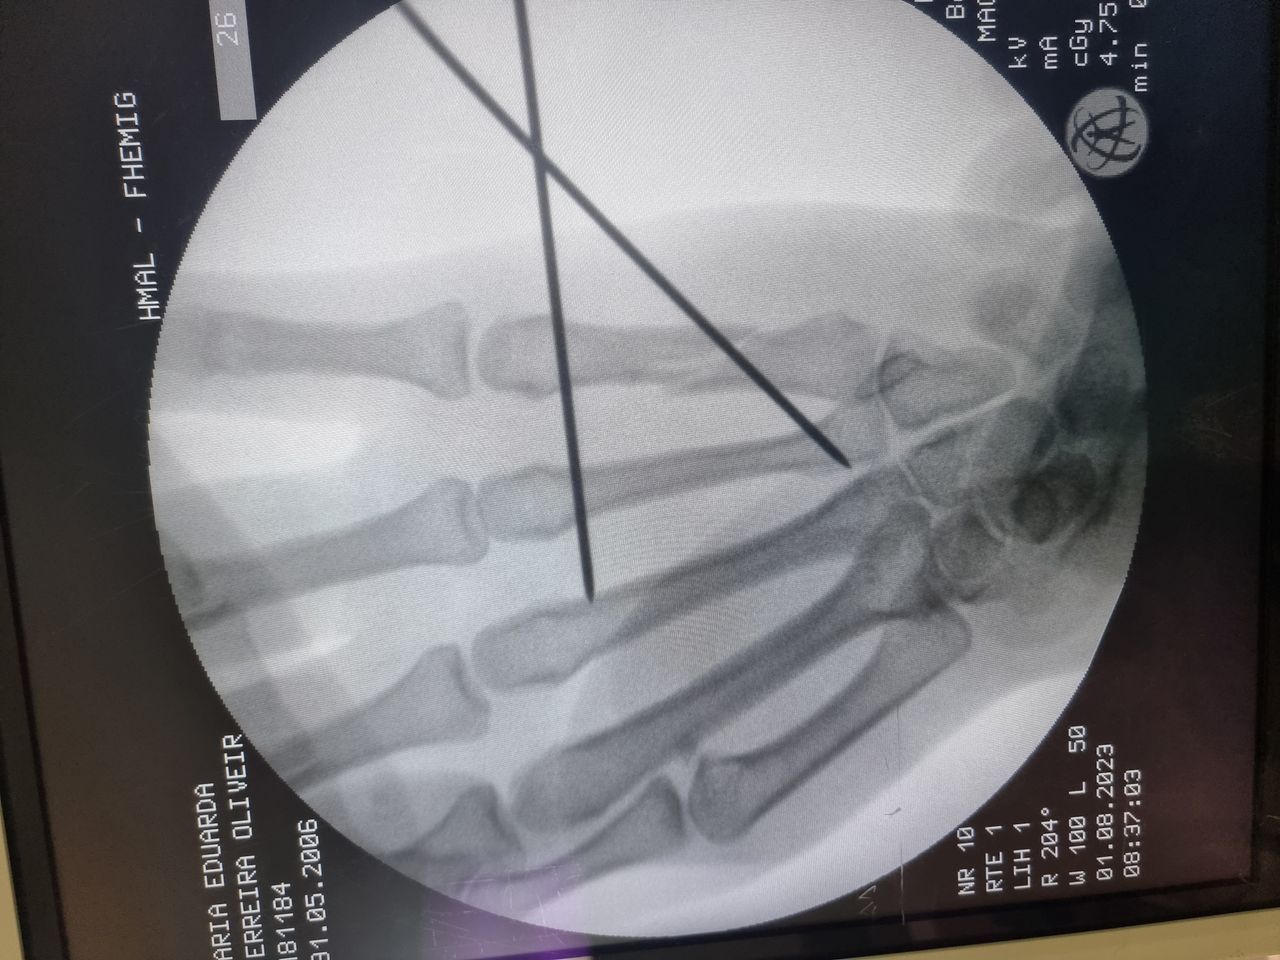

-ESCAFÓIDE: Tratamento da Fratura e da Pseudo-artrose do Escafóide com ou sem DISI e outras complicações, bem como Lesões Ligamentares da Mão e Punho, incluindo as do Ligamento Escafo-lunar do Carpo. Bennett, Rolando, Barton, Monteggia, Galleazzi e outras fraturas especiais ou comuns.

-FRATURAS: do antebraço, punho, metacarpos e  falanges.